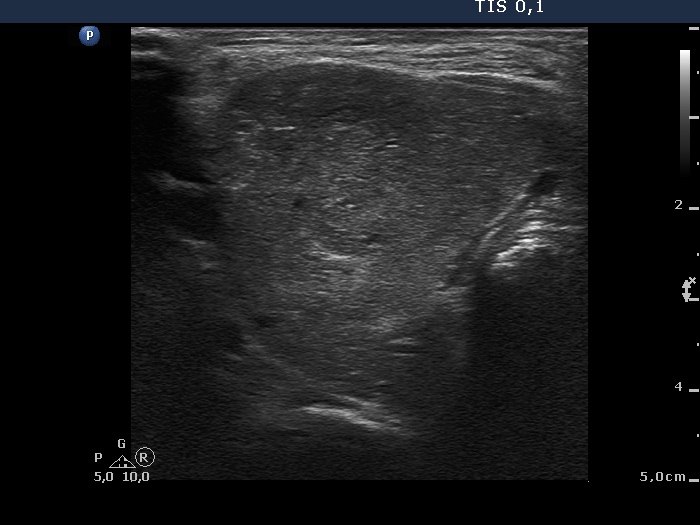

Ultrasonography. The thyroid was enlarged and contained numerous hyperechogenic nodules. There was a larger echonormal nodule in the ventrolateral part of the left lobe.

Cytology of one of the hyperechogenic nodules resulted in benign lesion.